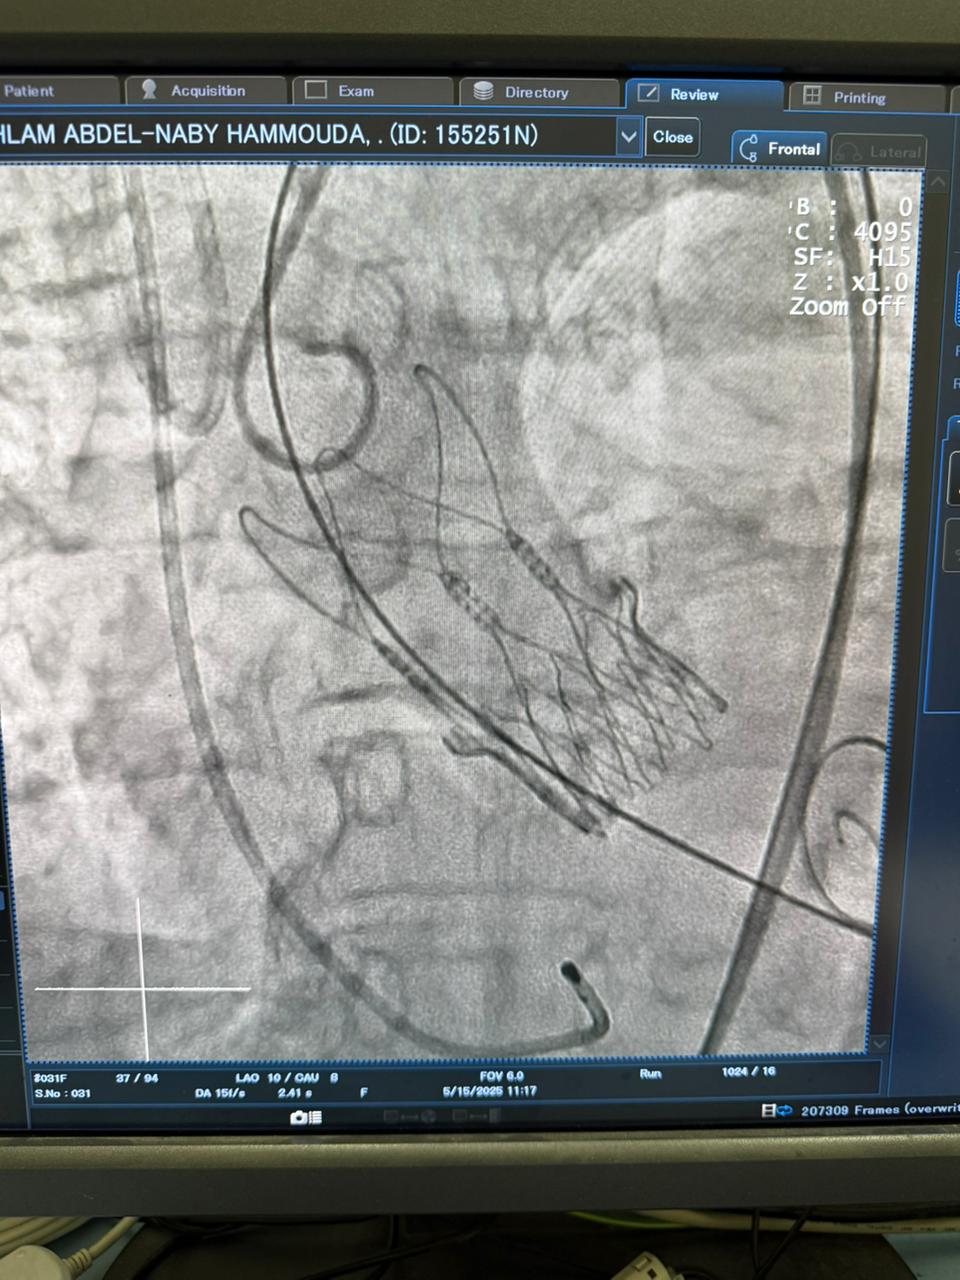

أعلنت وزارة الصحة والسكان، نجاح الفريق الطبي بأكاديمية قلب المبرة، بمستشفى مبرة مصر القديمة التابع للمؤسسة العلاجية، في زرع الصمام الأورطي بالقسطرة بواسطة تقنية (التافي) التي تعد أحدث طرق علاج ضيق الصمام بالقسطرة.

وأوضح الدكتور حسام عبدالغفار المتحدث الرسمي لوزارة الصحة والسكان، أن هذا التدخل الجراحي، كان لمريضة يتجاوز عمرها الـ70 عاما وكانت تعاني من ضيق شديد بالصمام الأورطي وتتعرض لإغماءات متكرر تهدد حياتها، مشيرا إلى أن فريق أكاديمية قلب المبرة يجري هذا التدخل الدقيق للمرة الـ52 خلال عامين، وبنسب نجاح توازي النسب العالمية.